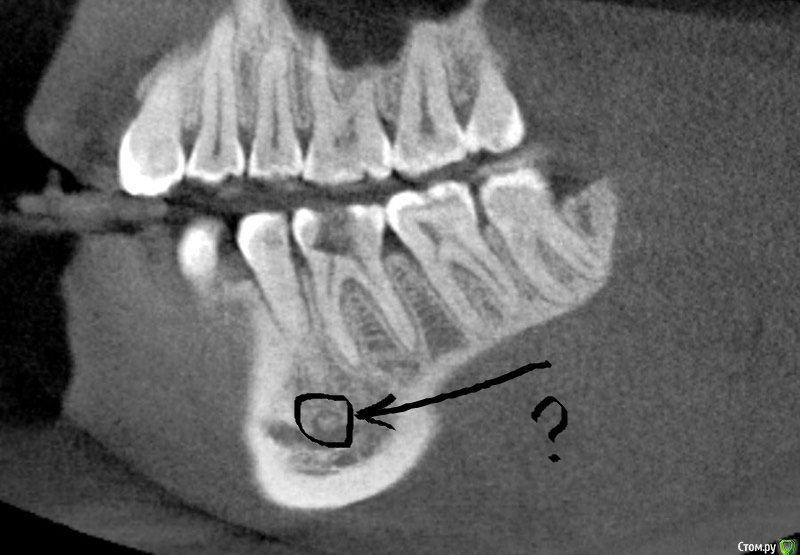

AlexanderGudkov Опубликовано 9 марта, 2016 Автор Поделиться Опубликовано 9 марта, 2016 Что кт? http://s017.radikal.ru/i416/1603/d1/018eb5f51a8e.png Ссылка на комментарий

kriokov Опубликовано 9 марта, 2016 Поделиться Опубликовано 9 марта, 2016 Коллеги, есть у кого-то какие-либо мысли? можете аксиальный срез залить на этом уровне? Ссылка на комментарий

AlexanderGudkov Опубликовано 9 марта, 2016 Автор Поделиться Опубликовано 9 марта, 2016 можете аксиальный срез залить на этом уровне?018eb5f51a8e.jpghttp://s019.radikal.ru/i605/1603/64/30d3c8fceb26.jpg Ссылка на комментарий

carloss Опубликовано 9 марта, 2016 Поделиться Опубликовано 9 марта, 2016 Карен, ты же умный! Скажи что-нибудь!Если судить по тому, что из принятых тут "умных" я единственный, кто не проводит курсов, то я себя таковым не считаю)) По теме - сложно сказать.. но не в каналах дело точно - вероятность того, что два рядом стоящих зуба одновременно так атипично среагировали близка к нулю.. да нормально там вроде все.. но решение по эндо принимались бы клинически. Заметно расширение периодонта на 5 и 6.. возможно это после орто так, а может из-за воспаления.. в любом случае похоже на острый "паро" процесс наверное как пишет Астронавт вследствие неспецефического микроба.. и, возможно, широкая щель послужила "широкими входными воротами" для микроба.. Я бы сразу начал с мощных доз антибиотиков(кстати всегда при воспалениях начинаю с комбинации амоксиклав+метронидазол, я думал все так), может через пару -тройку дней сменил бы. Правда под эту теорию не очень ложится то, что было уже с другой стороны раньше, но думается первичен именно микроб, остальное способствующие факторы. Еще не очень понравилось что-то на КТ, под пятеркой.. но наверное или ментальное или артефакт, думаю топикстартер разобрался бы, если что. но не факт, что не поступил бы как тут.. 5 Ссылка на комментарий

major Опубликовано 10 марта, 2016 Поделиться Опубликовано 10 марта, 2016 1. +1 к микробу2. 2 версия в порядке размышлений. Кт бы покрутить посмотреть, в области ментального отверстия возможно что-то есть. На памяти была схожая клиника была при сдавлении нижнечелюстного канала остеомой. В общем желательно сверить костный рисунок со "здоровой" стороной. Ссылка на комментарий

major Опубликовано 10 марта, 2016 Поделиться Опубликовано 10 марта, 2016 или кажется? Ссылка на комментарий

johniola Опубликовано 10 марта, 2016 Поделиться Опубликовано 10 марта, 2016 Нет там ничего,а даже если и есть,оно никак не связано с болью которую вы описали. 1 Ссылка на комментарий